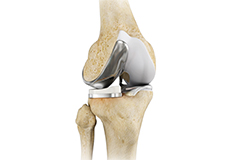

Total Knee Replacement

Total knee replacement, also called total knee arthroplasty, is a surgical procedure in which the worn out or damaged surfaces of the knee joint is removed and replaced with an artificial prosthesis.